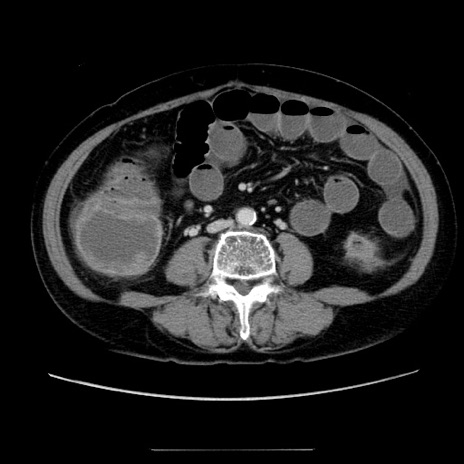

症例5(横断像)

【症例】70歳代女性

【主訴】お腹が張る

【現病歴】1週間くらい前から腹部膨満の自覚あり。昨日夜から増悪したため、本日救急外来受診。

【身体所見】意識清明、BT 36.5℃、BP 165/106mmHg、HR 80bpm、SpO2 98%、腹部:膨満、軟、自発痛・圧痛なし、触診にて不快感あり、腸蠕動音:減弱

【データ】WBC 12600、CRP 1.04